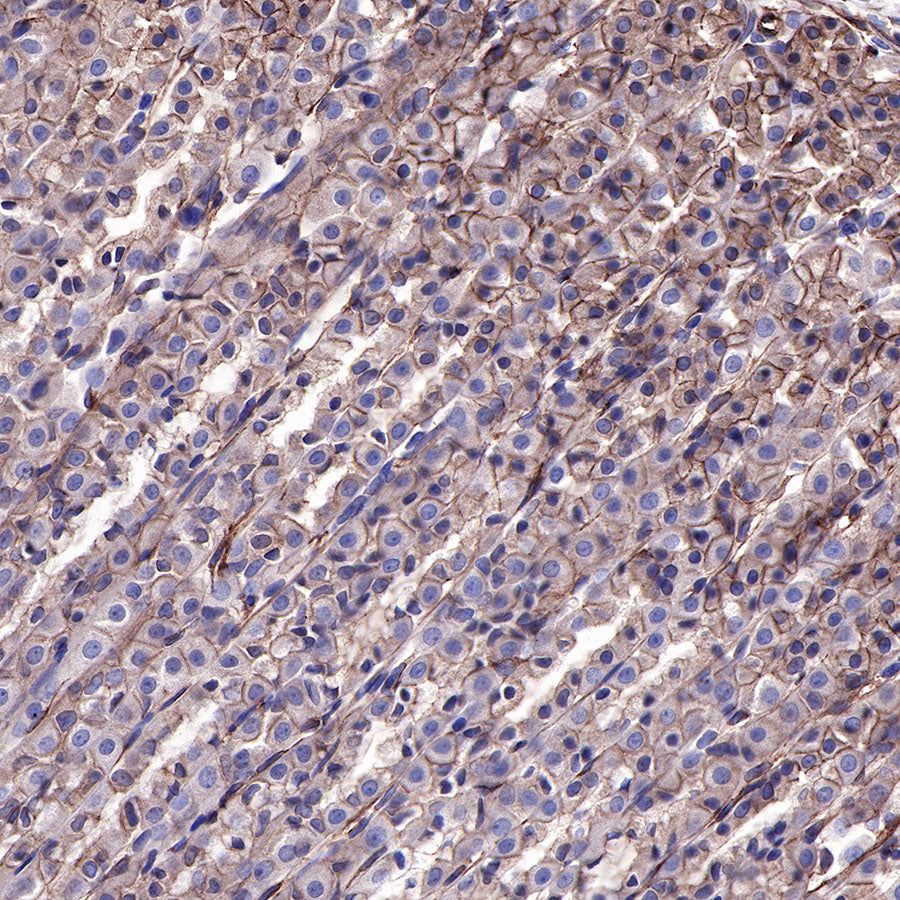

IHC shows positive staining in paraffin-embedded rat stomach. Anti-EGFR antibody was used at 1/500 dilution, followed by a HRP Polymer for Mouse & Rabbit IgG (ready to use). Counterstained with hematoxylin. Heat mediated antigen retrieval with Tris/EDTA buffer pH9.0 was performed before commencing with IHC staining protocol.